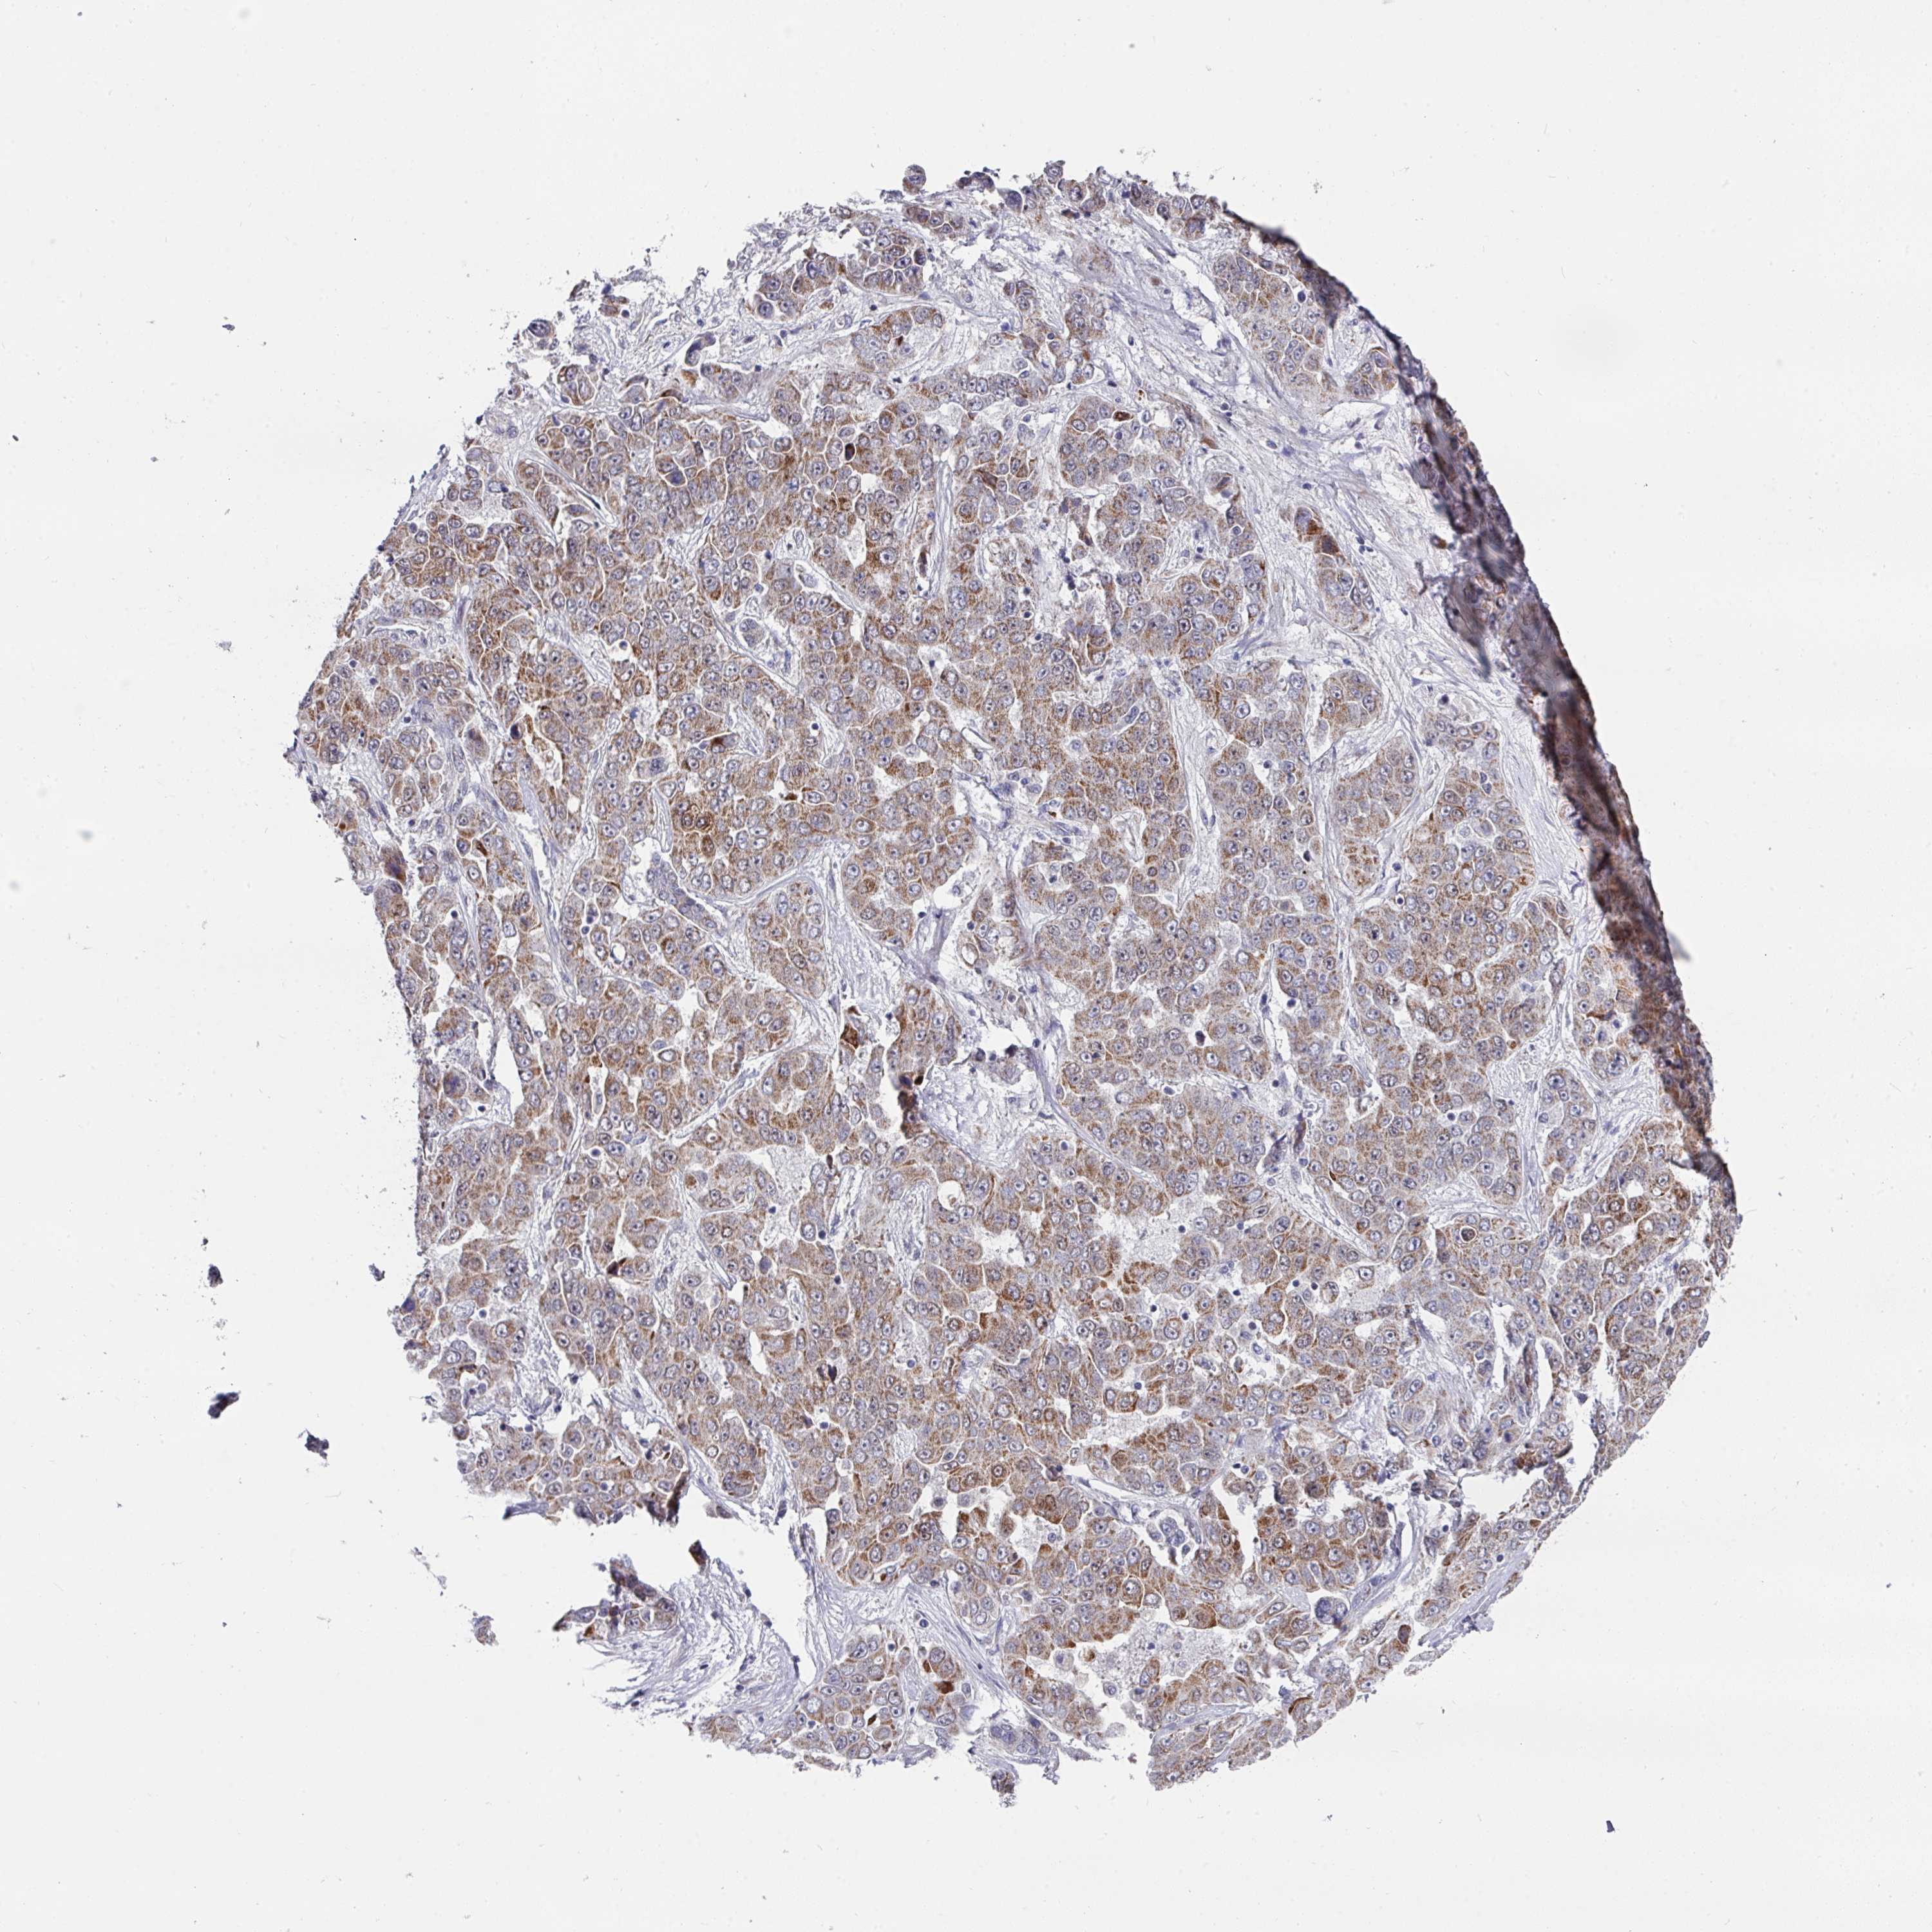

LIVER CANCER - Protein expressioni

A mouse-over function shows sample information and annotation data. Click on an image to view it in a full screen mode. Samples can be filtered based on level of antibody staining by selecting one or several of the following categories: high, medium, low and not detected. The assay and annotation is described here.

Note that samples used for immunohistochemistry by the Human Protein Atlas do not correspond to samples in the TCGA dataset.

Antibody stainingi

Antibody staining in the annotated cell types in the current human tissue is reported as not detected, low, medium, or high, based on conventional immunohistochemistry profiling in selected tissues. This score is based on the combination of the staining intensity and fraction of stained cells.

Each image is clickable and will lead to virtual microscopy that enables deeper exploration of all samples and also displays staining intensity scores, fraction scores and subcellular localization as well as patient and tissue information for each sample.

Antibody HPA048677

Antibody HPA056480

Antibody CAB011574

Staining

High

Medium

Low

Not detected

Intensity

Strong

Moderate

Weak

Negative

Quantity

>75%

75%-25%

<25%

None

Location

Nuclear

Cytoplasmic/membranous

Cytoplasmic/membranous,nuclear

Carcinoma, Hepatocellular, NOS

Cholangiocarcinoma